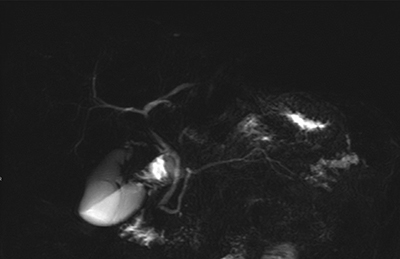

Magnetic resonance cholangiopancreatography showed a rare anatomical variant with duplication of the Wirsung duct along with a bifid appearance of the distal portion of the pancreas (Figures 3 and 4) and ductal alterations due to chronic pancreatitis were noted in the posterior tail.

Figure 4

MR cholangiopancreatography, RARE sequence showing caudal division of the Wirsung duct and chronic pancreatitis changes.